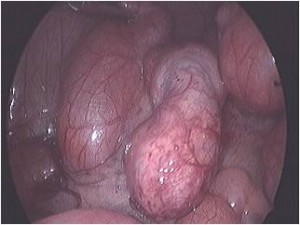

Acute Scrotum (Right scrotal Abscess)